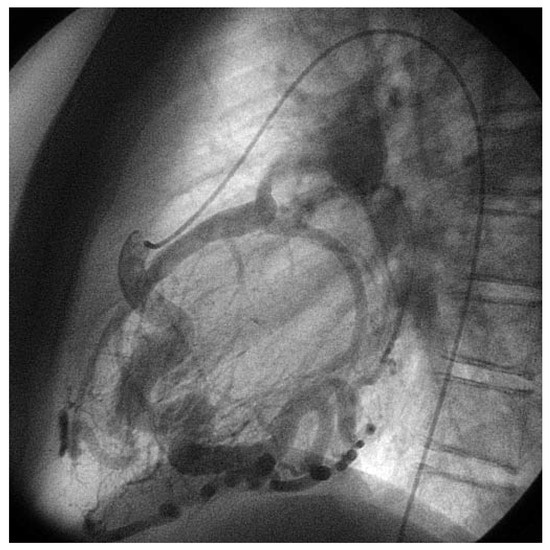

Asymptomatic Bland-White-Garland Syndrome in a 13-Year-Old Girl

by Jean-Pierre Pfammatter, Mladen Pavlovic and Stephan Windecker

An otherwise healthy 13-year-old girl was referred to the pediatric cardiology outpatient clinic for evaluation of a newly observed systolic murmur [...] Full article

Show Figures

Figure 1